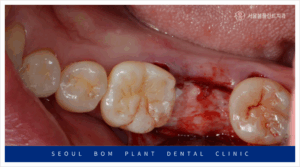

발치 후 3개월이 지난 뒤,

임플란트 식립을 위해 잇몸을 절개하고

골 내부 상태를 확인한 결과,

발치 당시 심한 염증이 있었던 부위가

잇몸뼈 회복이 더디게 이루어져

움푹 패인 상태를 보였습니다.

이렇게 잇몸뼈가 부족한 상태에서

무리하게 임플란트 식립을 하게 되면,

식립한 임플란트가 고정력을 얻지 못하게 되어,

결국 흔들리거나 금세 탈락하는 등의

문제가 발생할 수 있습니다.

이로 인해 임플란트의 장기적인

안정성을 확보하기 어려워지며,

임플란트의 기능을 제대로 발휘할 수 없습니다.

따라서, 임플란트를 오랫동안 건강하게

사용하기 위해서는 뼈이식이 필요한 경우가 많습니다.